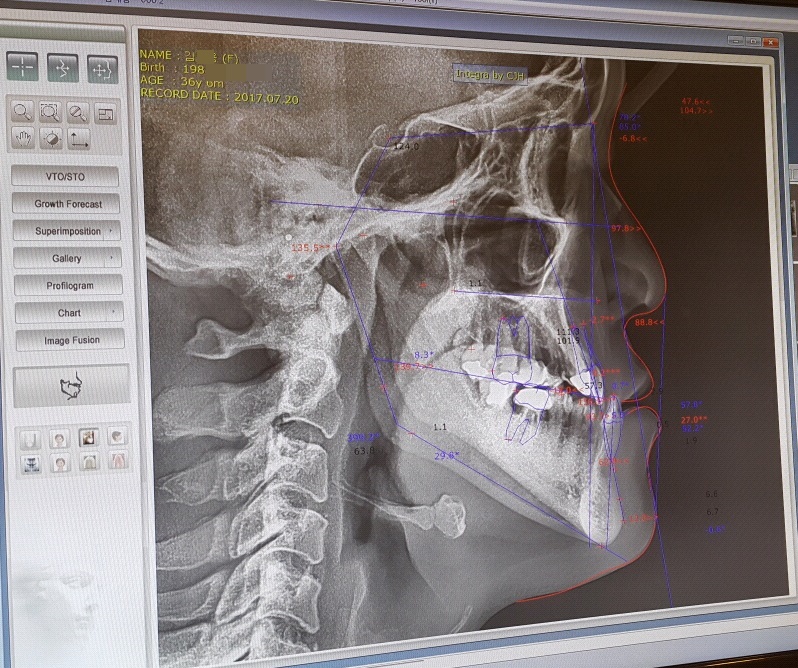

내 치아 상태는 위아래의 부정교합(이~ 했을 때 보통 사람들과는 조금 틀리게 밑의 치아가 윗 치아들을 덮는 반대교합)이 아주~ 심한 정도까지는 아니여도 그냥 보기에도 주걱턱이 확연히 들어나 있는 상황 이였다.

3년6개월에 거쳐 모든 과정이 끝난 지금의 내 치아상태인데

상악은 확실히 바뀐게 보이긴 한다..

그런데 밑의 앞쪽 치아들 중 한 치아는 강제로 이동되서 약간 비스듬히 뿌리가 잡혀있는게 보인다.